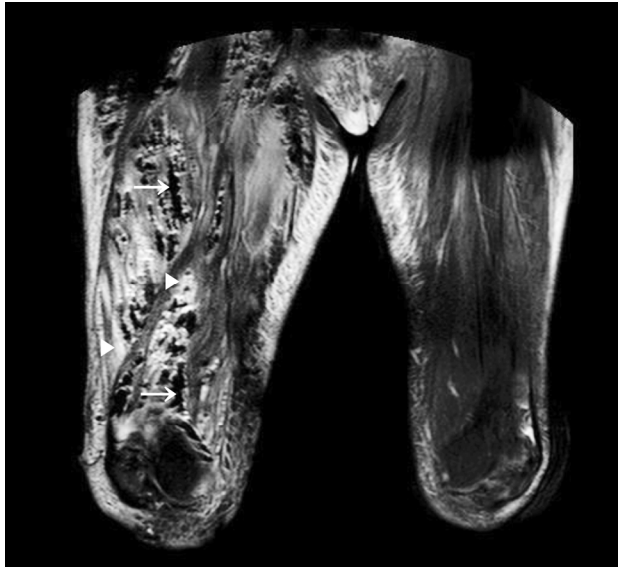

Figure 2.

T2-weighted MRI (fat suppression) shows diffuse low signal intensities (→) suggesting air and high signal intensities (▷) suggesting edema in the muscle layer. MRI, magnetic resonance imaging.

환 자: 57세 여자주호소: 오른쪽 무릎 통증과 부종현병력: 내원 7일 전 가위에 오른쪽 무릎을 찔린 후 2일째 부터 무릎 통증이 발생하여 동네 병원을 방문해 화농성 관절염의 진단 하에 항생제 치료를 하였으나, 무릎 통증과 부종, 발열 등의 임상증상이 호전되지 않고 악화되어서 본원으로 내원함과거력: 8년 전 고혈압과 당뇨병으로 진단받은 후부터 약물치료 중이며, 같은 해에 자궁근종으로 자궁절제술을 시행함가족력/사회력: 특이소견 없음이학적 소견: 응급실 내원 당시 혈압 120/64 mmHg, 맥박 99회/분, 호흡수 24회/분, 체온 38.5℃였다. 의식은 명료하고 급성 병색 소견을 보였다. 오른쪽 무릎과 넓적다리에 부종, 발적과 함께 열감, 압통, 마찰음(crepitus)이 촉지되었다.검사실 소견: 말초혈액 검사에서 백혈구 10,200/mm2 (호중구 85.8%)로 증가되어 있었고, 혈색소 8.2 g/dL로 감소되어 있었으며, 혈소판 182,000/mm2로 정상이었다. 생화학 검사에서 아스파르테이트아미노전달효소(AST)가 50 IU/L (참고치 10-45)로 약간 증가되었고, 알라닌아미노전달효소(ALT) 12 IU/L (참고치 10-45), 알카리인산분해효소(ALP) 72 IU/L (참고치 42-121), 총빌리루빈(T. bilirubin) 0.4 (참고치 0.2-1.2)로 정상 범위에 있었다. 혈액요소질소(blood urea nitrogen) 39 mg/dL (참고치 7-18)로 증가된 반면 크레아티닌(Cr)은 0.6 mg/dL (참고치 0.6-1.2)로 정상이었다. 총단백 4.6 g/dL (참고치 6.5-8.3), 알부민 1.7 g/dL (참고치 3.6-5.5)로 감소되어 있었고, 적혈구침강속도(erythrocyte sedimentation rate) 120 mm/h (참고치 0-20), C-반응단백(C-reactive protein) 238.3 mg/L (참고치 0-5.0)로 증가되어 있었다. 혈청 검사에서 B형간염표면항원과 항체가 모두 음성이었고 C형간염항체도 음성이었다.방사선 소견: 단순 방사선 사진에서 오른쪽 무릎관절 주변과 대퇴부에 가스 음영이 관찰되었고(Fig. 1), 자기공명영상에서는 오른쪽 무릎관절 및 대퇴부의 대부분 근육에 부종과 가스 음영이 관찰되었다(Fig. 2).치료 및 경과: 가스 괴저로 인한 패혈증으로 진단하고 penicillin G 500 M units q 6 hrs, clindamycin 600 mg q 8 hrs 그리고 ceftriaxone 2 g q 24 hrs을 투약하였다. 그리고 응급으로 괴사조직제거술과 세척술을 시행하였는데, 당시 피부절개를 한 후에 확인한 근육병변에서 심한 악취가 났다. 또한 오른쪽 대퇴사두근 중에서 일부를 제외한 대부분의 근육이 괴사가 되어서, 괴사된 대부분의 조직을 제거하였다(Fig. 3). 혈액 배양은 음성이었으며 수술장에서 시행한 괴사조직배양 검사에서 페니실린에 감수성이 있는 Streptococcus anginosus가 배양되었다. 항생제는 ceftriaxone 2 g q 24 hrs과 clindamycin 600 mg q 8 hrs으로 투여하고, 매일 병변 부위를 소독하면서 괴사조직에 대해서 조직제거술을 시행하였다. 수술 후 12일째에 환자에서 발열이 있으면서 수술부위에서 농이 발생하여 농에 대한 배양 검사를 시행하였다. 배양 검사에서 carbapenem-resistant Acinetobacter baumannii가 동정되어서, 항생제는 Imipenem 500 mg q 6 hrs과 Ampicillin/sulbactam 3 g q 6 hrs의 병합요법을 시행하였다. 이후에 발열이 호전되고, 수술병변도 농이 없어지면서 다시 좋아지는 소견을 보였다. 내원 첫날부터 19일간 괴사조직제거술과 세척술을 시행한 후에는 병변에 대해서 소독만 시행하였고, 항생제는 총 59일간 투여하였다. 이후에 다리의 병변 부위가 모두 좋아져서 오른쪽 목발 보행을 위한 재활 치료를 하였다. 재활 치료를 하면서 걸을 때 오른쪽 발을 저는 후유증을 제외한 모든 증상이 호전되어서 71일 이후에 퇴원하였다.